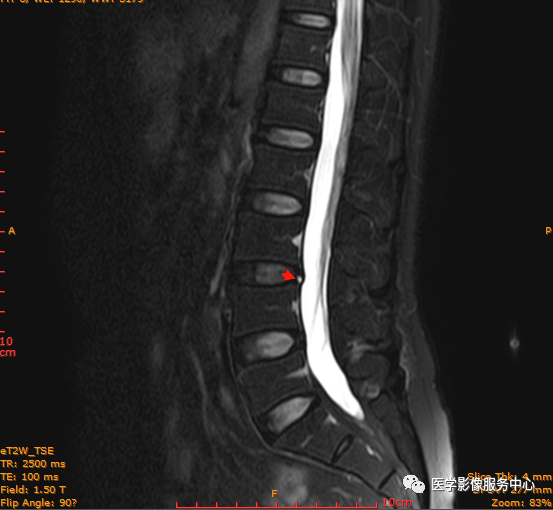

T2矢状位

这个患者腰椎间盘膨出程度不明显,神经根没有明显的受压,椎管未见明显狭窄,那这个患者腰疼的“罪魁祸首”是腰椎间盘膨出嘛?

L3-4椎间盘后缘可见点状高信号区(红色箭头所指处)

红色箭头所指的异常信号区是是什么呢?平时工作中大家有没有遇到这种情况,你会不会忽略这个异常信号?有没有想过这个椎间盘后缘高信号区是引起患者腰疼的重要因素呢?下面为大家重点介绍。

腰椎椎间盘高信号区是诊断椎间盘源性腰痛的重要MRI征象,且在急性重度下腰痛患者中更明显。HIZ 由 Aprill 和 Bogduk 在1992年首次描述,即 矢状位MRI T2加权像显示腰椎间盘后缘小而圆或线状的局限性高信号区。

影像表现主要在T2矢状位及T2横断位可见椎间盘前缘或后缘可见高信号区;

日常工作因腰腿疼痛来检查腰椎MRI的很多,而腰腿疼痛并不一定就是腰椎椎间盘突出或膨出导致的,我们应该需要知道椎间盘HIZ也会引起腰腿疼痛,这种椎间盘源性的疼痛我们不能“忽略”;椎间盘后方HIZ并不少见,椎间盘后方 HIZ 在 T2WI 的局限性高信号、T1WI 呈局限性较低或等信号意味着通常所指的纤维环破裂伴随肉芽组织长入;而 T1WI、T2WI 均呈高信号可能是钙化组织。